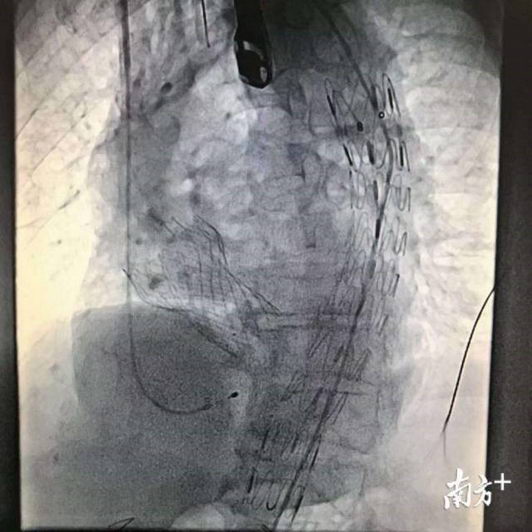

TAVR+TEVAR手术影像。

与彭姨及家属沟通后,2月22日,在配备了医疗成像设备的复合手术室内,罗建方团队进行了经导管主动脉瓣置换术联合胸主动脉腔内修复术(TAVR+TEVAR)的一站式微创手术。

在对患者进行全身麻醉后,医生用穿刺针把一个自膨式的人工生物瓣膜用一根很细的导管,从股动脉导入到心脏主动脉原先病损的瓣膜处。“这好比把原先病损的瓣膜当‘门框’,将新导入的瓣膜用球囊锚定在这个‘门框’上,作为新的‘心门’。”罗建方做了一个形象的比喻。

之后,医生又通过类似的路径,把处于压缩状态的覆膜支架送达胸主动脉病变位置,准确定位后,将其释放,扩张后的覆膜支架覆盖透壁性溃疡处,隔绝血管病变部位并形成新的血流通道,以达到治疗目的。